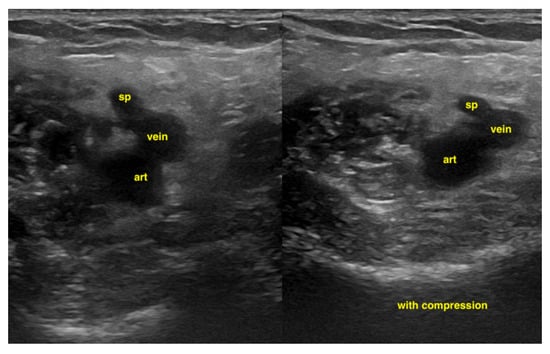

7.4.3. Deep Vein Thrombosis

An examination of the veins is usually performed with a linear transducer. Deep vein thrombosis is most reliably detected through compression sonography, although it may be obvious as an echogenic entity within the vessel lumen in some cases. The probe is in a transverse orientation with respect to the vessel. With pressure in a perpendicular vector on the vein, the vessel should collapse completely. It is important in this clinical situation to decide if there is a central pulmonary embolism too. In a peri-arrest situation, it is enough to apply a two-point compression ultrasound (inguinal and popliteal). Color Doppler is rarely required and would only be used to identify the location of vessels, as the examination relies solely on venous compression [] (Figure 19). Possible additional signs in deep vein thrombosis can be found by looking for signs of central pulmonary embolism.

Figure 19.

In the popliteal 4-region, the popliteal vein and the saphena parva vein cannot be compressed due to a thrombus.